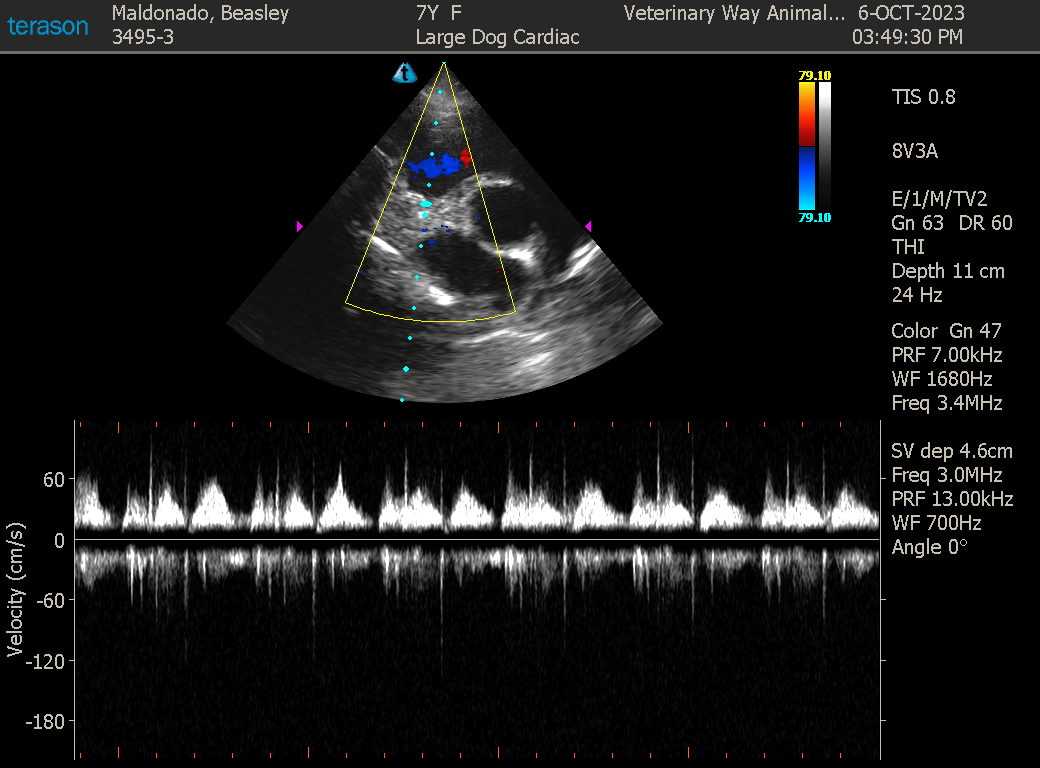

- Heart Health: Performing echocardiograms to evaluate heart murmurs or valve function.

- Collaborative Care: When a case requires additional insight, we collaborate closely with board-certified internal medicine specialists and radiologists. This ensures a comprehensive interpretation of every scan and expert-level care for even the most complex cases.

- Precision & Compassion: From routine abdominal scans to more complex diagnostic cases, our ultrasound services help us deliver precise, compassionate care every step of the way.